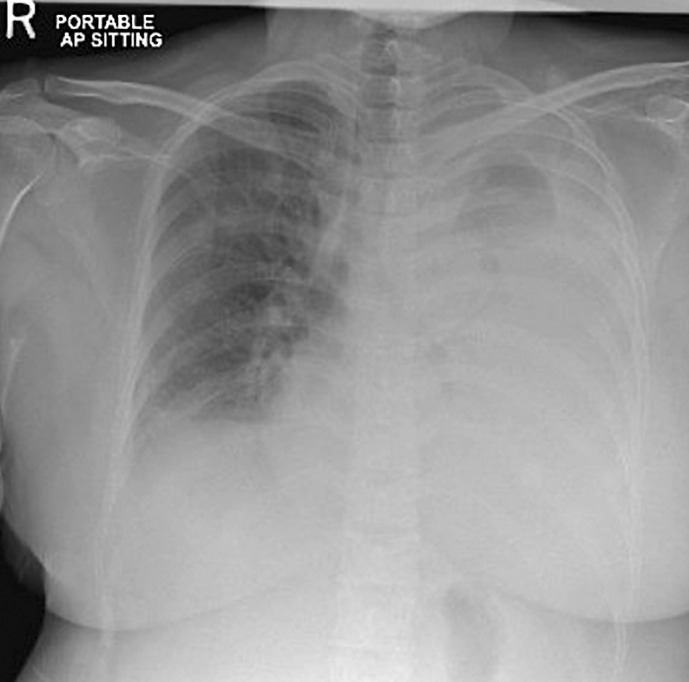

Case presentation: A 42-year-old Asian female presented with left shoulder pain and swelling, leading to the diagnosis of IgG lambda MM with extensive extramedullary disease. After initial partial response to D-VRD therapy, she developed MPE with complete left lung collapse. Following failure of second-line KPD-PACE therapy, she received teclistamab, achieving complete metabolic and morphological response documented by PET-CT. After maintaining remission for 10 months, she experienced relapse with pericardial involvement presenting as cardiac tamponade.

Conclusion: The patient demonstrated an unprecedented response to BCMA-targeted therapy with teclistamab, achieving complete remission that lasted 10 months - more than doubling the historical median survival of 4 months for MPE. Flow cytometry proved instrumental in rapid diagnosis, showing 11% lambda monotypic plasma cells in the pleural fluid. The subsequent pericardial involvement after initial complete response highlighted the persistent challenges in managing extramedullary disease. This case represents the first documented instance of sequential MPE and pericardial involvement in MM, demonstrating the potential of novel targeted therapies, particularly BCMA-directed approaches, in extending survival and improving outcomes in these rare but aggressive disease manifestations.